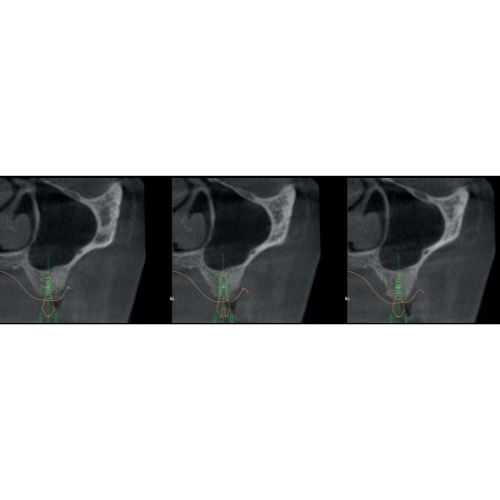

X-MIND® optima 3D represents the perfect combination of advanced hardware technology, enclosed in a lightweight and compact design and next-generation software, RealGuide™ 5.4, bringing the benefits of Artificial Intelligence into every step of patient care, from a precise diagnosis to more effective treatments and patient communication.

- 2D and 3D Imaging

- Adjustable FOV